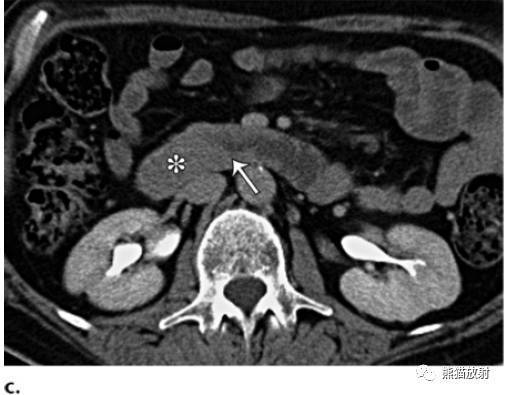

什么是十二指肠癌?